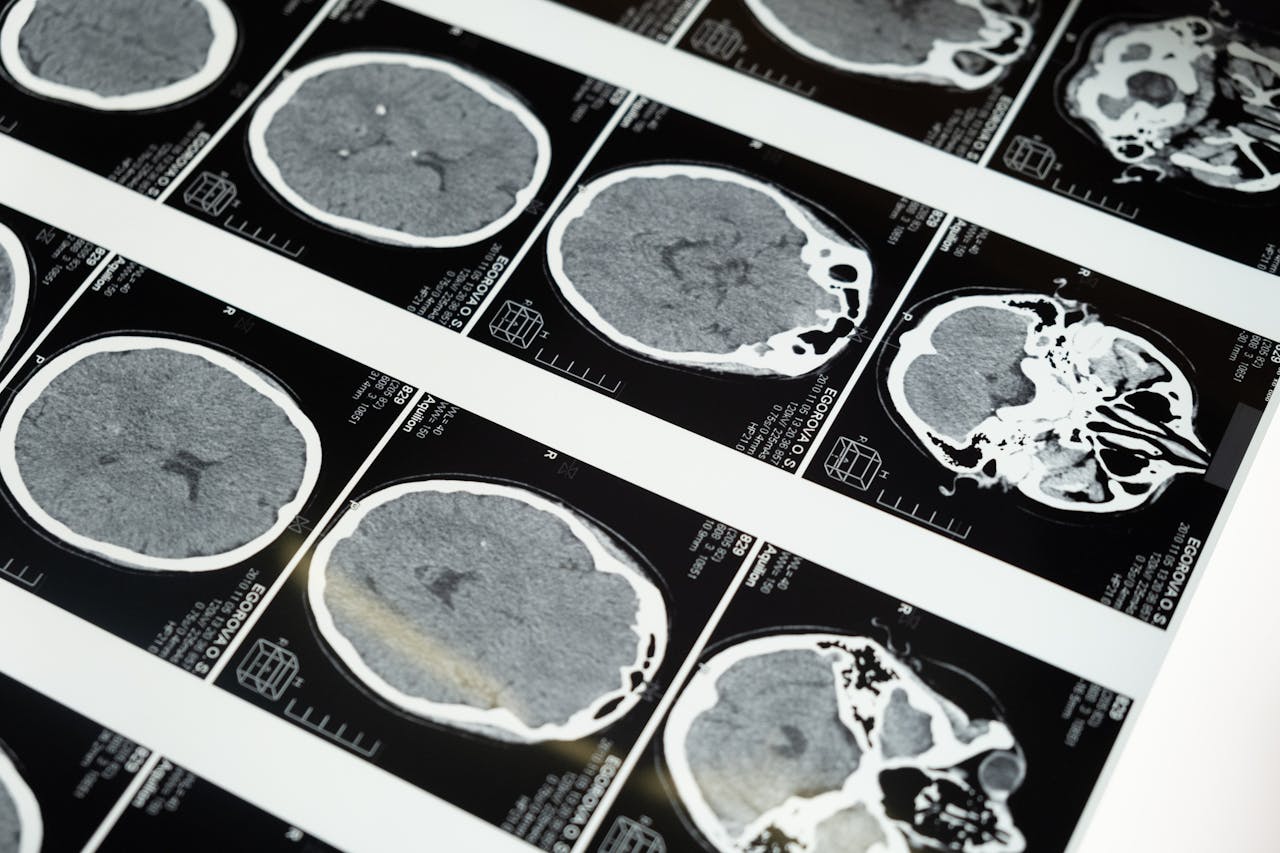

I trattamenti neurologici proposti dal Dr. Attilio Conte sono pensati per gestire diverse condizioni, dalle più comuni alle più complesse. Dopo una valutazione approfondita, viene definito un piano terapeutico personalizzato che può includere terapia farmacologica, monitoraggio clinico e indicazioni pratiche per la gestione quotidiana dei sintomi. Particolare attenzione viene data a disturbi come emicrania, tremori, neuropatie e deficit cognitivi. L’obiettivo è ridurre i sintomi e migliorare la funzionalità, con un percorso costruito su misura.

La visita specialistica neurologica rappresenta il primo passo per comprendere l’origine di disturbi come vertigini, perdita di memoria, formicolii o difficoltà motorie. Durante la visita, il Dr. Attilio Conte raccoglie informazioni dettagliate, esegue un esame neurologico completo e, se necessario, consiglia ulteriori approfondimenti diagnostici. Questo approccio permette di arrivare a una diagnosi chiara e di impostare un percorso terapeutico efficace. La visita è strutturata per essere chiara, approfondita e orientata alla soluzione.